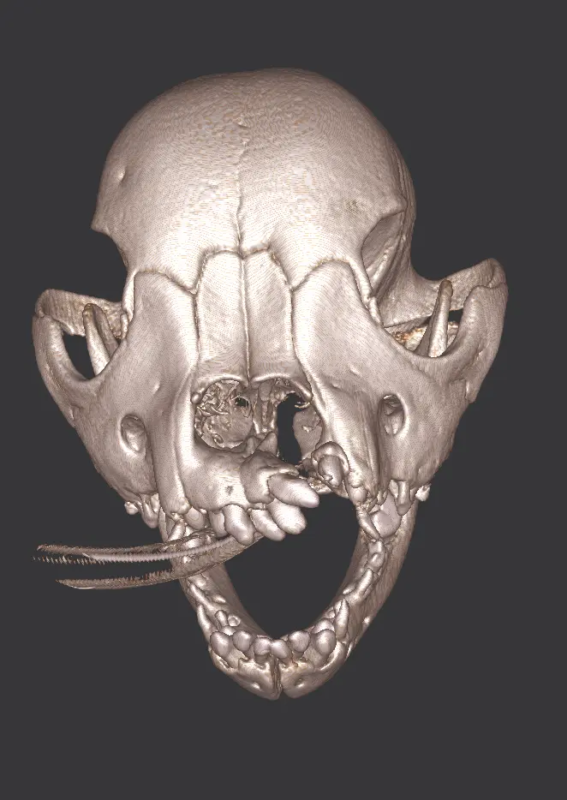

The Center now provides advanced imaging via cone beam CT. Cone beam CT is excellent for visualization of bony structures of the skull, nasal cavity, teeth, and ears. Cone beam CT is especially helpful for diagnosing dental disease and evaluation of jaw fractures. It can also be useful for evaluating the sinuses and tympanic bulla. Cone beam CT can be used in conjunction with nasal biopsy and culture to evaluate nasal discharge whether chronic or acute.

Tumors of the Maxilla, Mandible and Facial Area

Oral tumors are very common in dogs and cats. Many of these tumors can be successfully removed with surgery. Benign tumors can be cured with surgery alone, and malignant tumors can be treated with surgery and some combination of radiation or chemotherapy. In many cases oral tumors cause a great degree of discomfort or are bleeding and need to be removed to allow your pet to be more comfortable.

Pets can be involved in trauma that can cause fractures to their head, teeth, and jaw bones. Correctly repairing these fractures is extremely important for your pet to have normal function of their mouth. If a jaw fracture is allowed to heal in an abnormal position, your pet may have great difficulty chewing and can be in significant pain. Many fractures can be successfully treated with minimally invasive oral procedures, but more complicated cases may require bone plating techniques. The Center offers cone beam CT imaging which provides extremely detailed images of the bones of the head and skull. Advanced imaging with CBCT facilitates selection of the best surgical technique to get your pet back to eating and comfort as soon as possible.